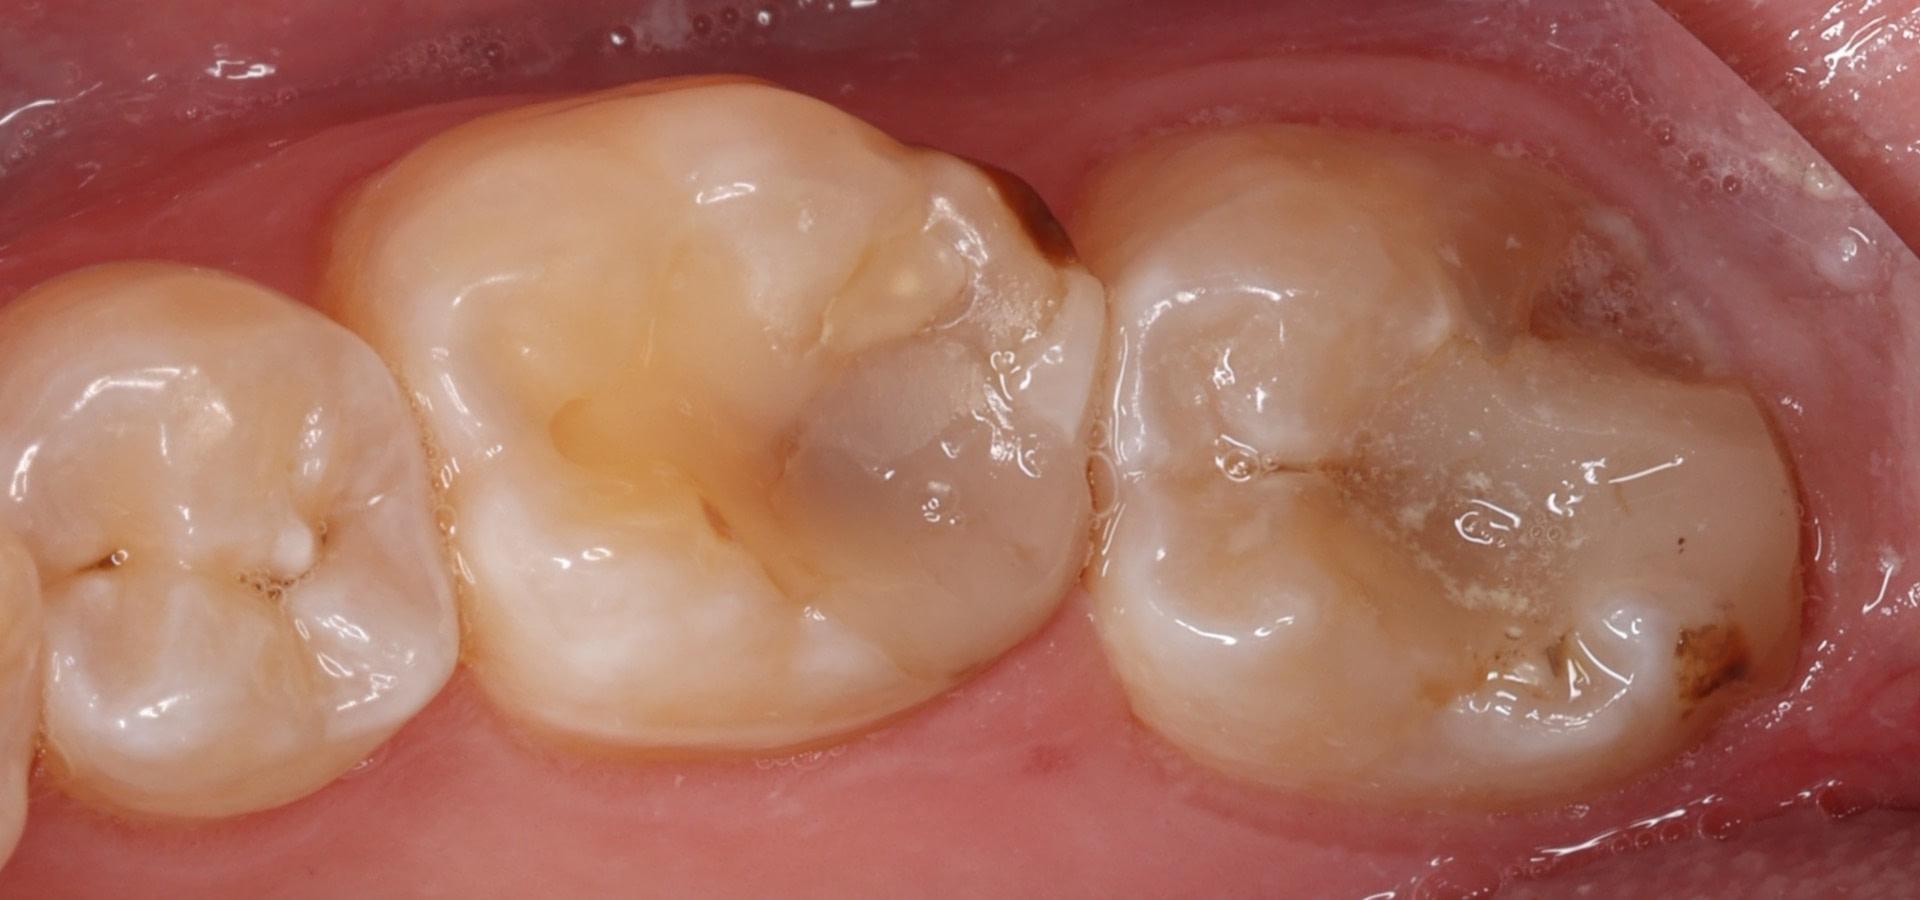

First, I prepared the tooth for the restoration. Before picking up your Medit scanner, you should have cleaned the tooth sufficiently and carried out your tooth preparation depending on your tooth preparation type and material of choice.

Then, the key part, retract the gingiva to enable a clear scan, and in this case, I use a retraction cord.

Then, as usual, the vital part of the process, the data collection. Using an intraoral scanner, I captured a digital impression, which I will use to design the restoration.

The better the soft tissues are retracted, the better and faster your scan will be. The beauty of digital impressions is that if you miss some data, you can always rescan.